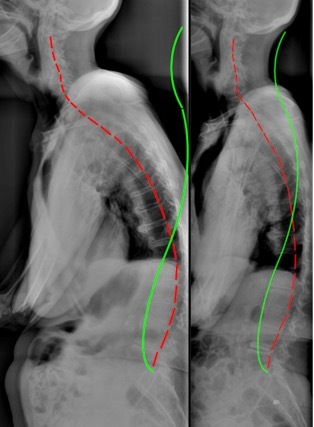

Radiographic examination was performed (Figure 1) and spinal alignment was measured by digitizing the images in the PostureRay software system (PostureCo. Inc., Trinity, FL, USA). This system used the Harrison posterior tangent method to measure regional and intersegmental vertebral angles and distances.7–10

The patient had extreme anterior sagittal balance, 175.2mm, as measured from the horizontal displacement from C1-S1, or 145.1mm, as measured from T1-S1. The lumbar lordosis L1-L5 measured +13.2° (vs. -40° normal11,12), the thoracic kyphosis T1-T12 measured 37.9° (vs. 44° normal13), and the cervical lordosis C2-C7 measured -28.4° (vs. normal -29-42°14–16). The forward head translation as measured as the horizontal distance from the posterior-superior C2 vertebral body corner to the vertical line drawn from the posterior-inferior C7 vertebral body corner measured 31.4mm (normal <15mm14,15).

Radiographic assessment revealed significant reduction in anterior sagittal balance (Fig. 1). The C1-S1 sagittal balance reduced to 66.5mm (vs. 175.2mm) and the T1-S1 sagittal balance reduced to 47.5mm (vs. 145.1mm). The lumbar lordosis improved to be slightly lordotic (-1.6° vs. +13.2°), the thoracic kyphosis increased towards normal (40.6° vs. 37.9°), and the cervical lordosis increased to within normal limits (37.3° vs. 28.4°). Anterior head translation reduced to 15.5mm (vs. 31.4mm).